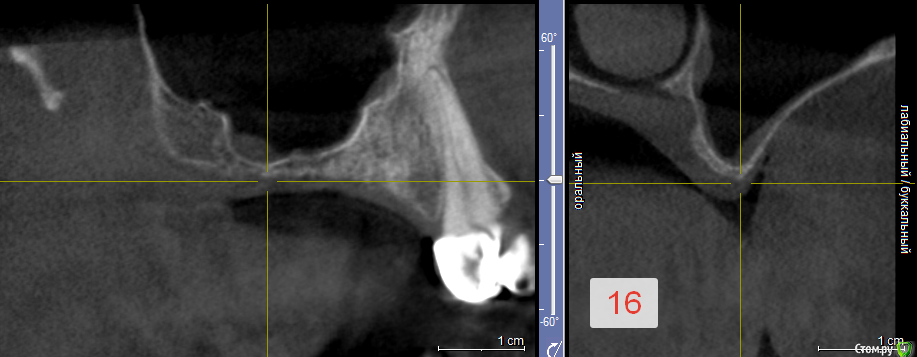

MaksimKardash Опубликовано 31 мая, 2017 Поделиться Опубликовано 31 мая, 2017 (изменено) Добрый вечер, коллеги! Что вы делаете, когда на верхней челюсти в боковом сегменте узкий короткий гребень на фоне гиперпневматизации (26)?Хотелось бы как-то справиться полужёстким каркасом одновременно с синус-лифтингом. Хватит ли у кости на это потенциала, и как долго надо ждать? Просто ещё не было таких ситуаций. И попутно ещё такой вопрос: сколько ждать после синуса в таких случаях (16)?Заранее благодарю всех за ответ!))) Изменено 31 мая, 2017 пользователем MaksimKardash Ссылка на комментарий

syrovovec Опубликовано 31 мая, 2017 Поделиться Опубликовано 31 мая, 2017 Просто синус лифтинг, 26 заглубить. Жду почти всегда пол года Ссылка на комментарий

dok1 Опубликовано 31 мая, 2017 Поделиться Опубликовано 31 мая, 2017 С измерениями скриншоты бы... Но особых проблем не вижу. Все в один присест. Ссылка на комментарий